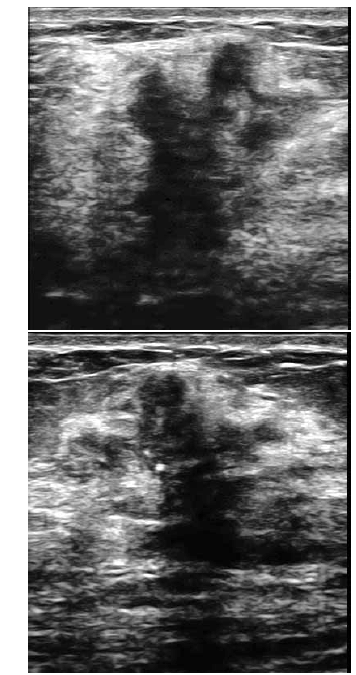

Uma paciente de 32 anos de idade procurou um médico ginecologista por ter palpado nódulo na mama direita. Ao exame das mamas, foi percebido nódulo endurecido, fixo aos planos adjacentes, com cerca de 3 cm de diâmetro. Foi realizada, então, mamografia, que revelou presença de lesão espiculada, com limites imprecisos, retração do parênquima adjacente e microcalcificações pleomórficas agrupadas. O exame ultrassonográfico evidenciou a lesão representada na forma gráfica na figura abaixo.

Segundo a classificação do BI-RADS ultrassonográfico, essa imagem poderia ser enquadrada na categoria IV-b.